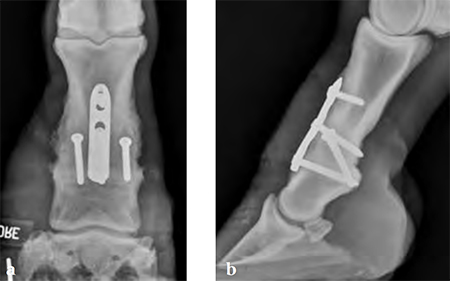

Horse with degenerative joint disease of the proximal interphalangeal joint (narrowed joint space and periosteal new bone formation).

(Case provided by Jeffrey Watkins, Tamu, USA)

Compression across the joint was achieved by placing the abaxial transarticular 5.5 mm cortical screws in lag fashion, then using the cortex screw in the load position of the proximal combination hole. The screws on either side of the joint are 5.0 mm locking screwsthe most distal screw is placed first, then the cortex screw is used to provide dynamic compression and the final locking screw is placed.